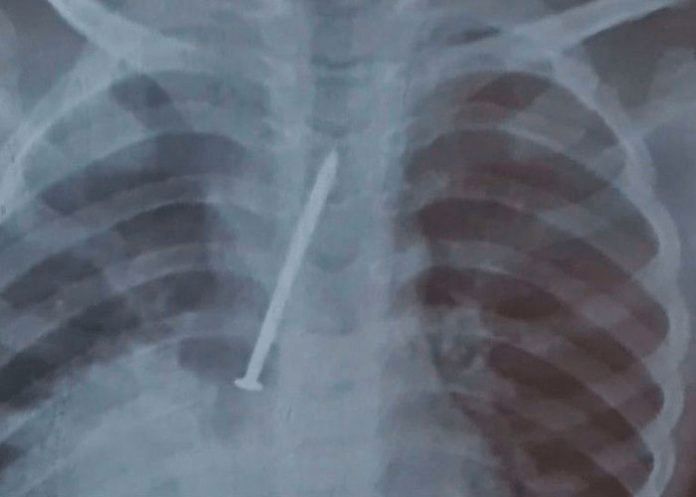

Niño muere luego de pasar un año con un clavo en sus pulmones

Un niño de 3 años de Brasil, murió por un clavo incrustado en sus pulmones, tras pasar un año con el clavo luego de habérselo tragado situación que lo llevó a la muerte.

Los rayos x terminaron confirmando que había un objeto extraño en el cuerpo y decidieron operar. A pesar del esfuerzo ya el clavo había hecho daño en sus pulmones.